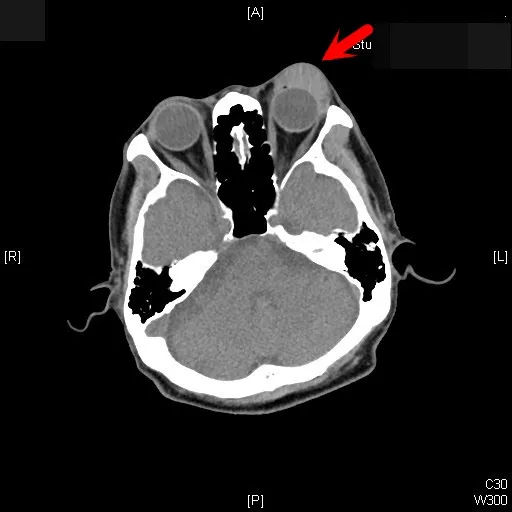

電腦斷層影像中,可看見大叔左眼明顯往外凸。張丞賢醫師提供

張丞賢表示,經以外力翻開大叔左眼皮,發現大叔左眼球根本轉不動,即使張開,也會有左、右眼無法對焦、複視困擾,隨即安排他做電腦斷層,果真發現一顆腫瘤,就在左眼球後方。

確定左眼球後方「長東西」,大叔被全身麻醉手術,取出這顆比眼球還大、如乒乓球的腫瘤,病理證實是「眼窩淋巴癌」,由於腫瘤壓迫支配左眼皮、眼球轉動神經,才無法睜開與轉動眼珠,若晚點開刀,腫瘤壓迫視神經,即可能失明。